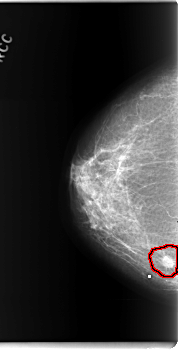

C_0202_1.LEFT_CC

FILE: C_0202_1.RIGHT_CC.OVERLAY

TOTAL_ABNORMALITIES 1

ABNORMALITY 1

LESION_TYPE MASS SHAPE ROUND MARGINS SPICULATED

ASSESSMENT 5

SUBTLETY 5

PATHOLOGY MALIGNANT

TOTAL_OUTLINES 1

BOUNDARY